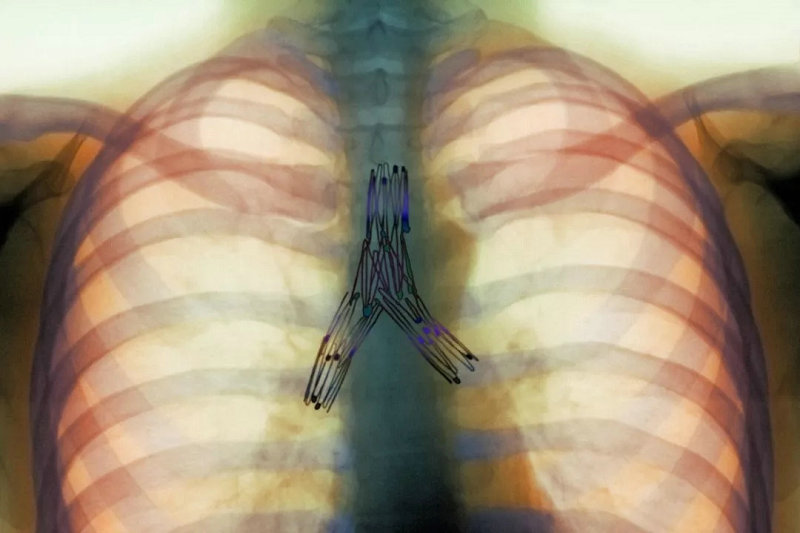

▲ 红色箭头为狭窄的气道

▲ 红色箭头为扩张的气道支架